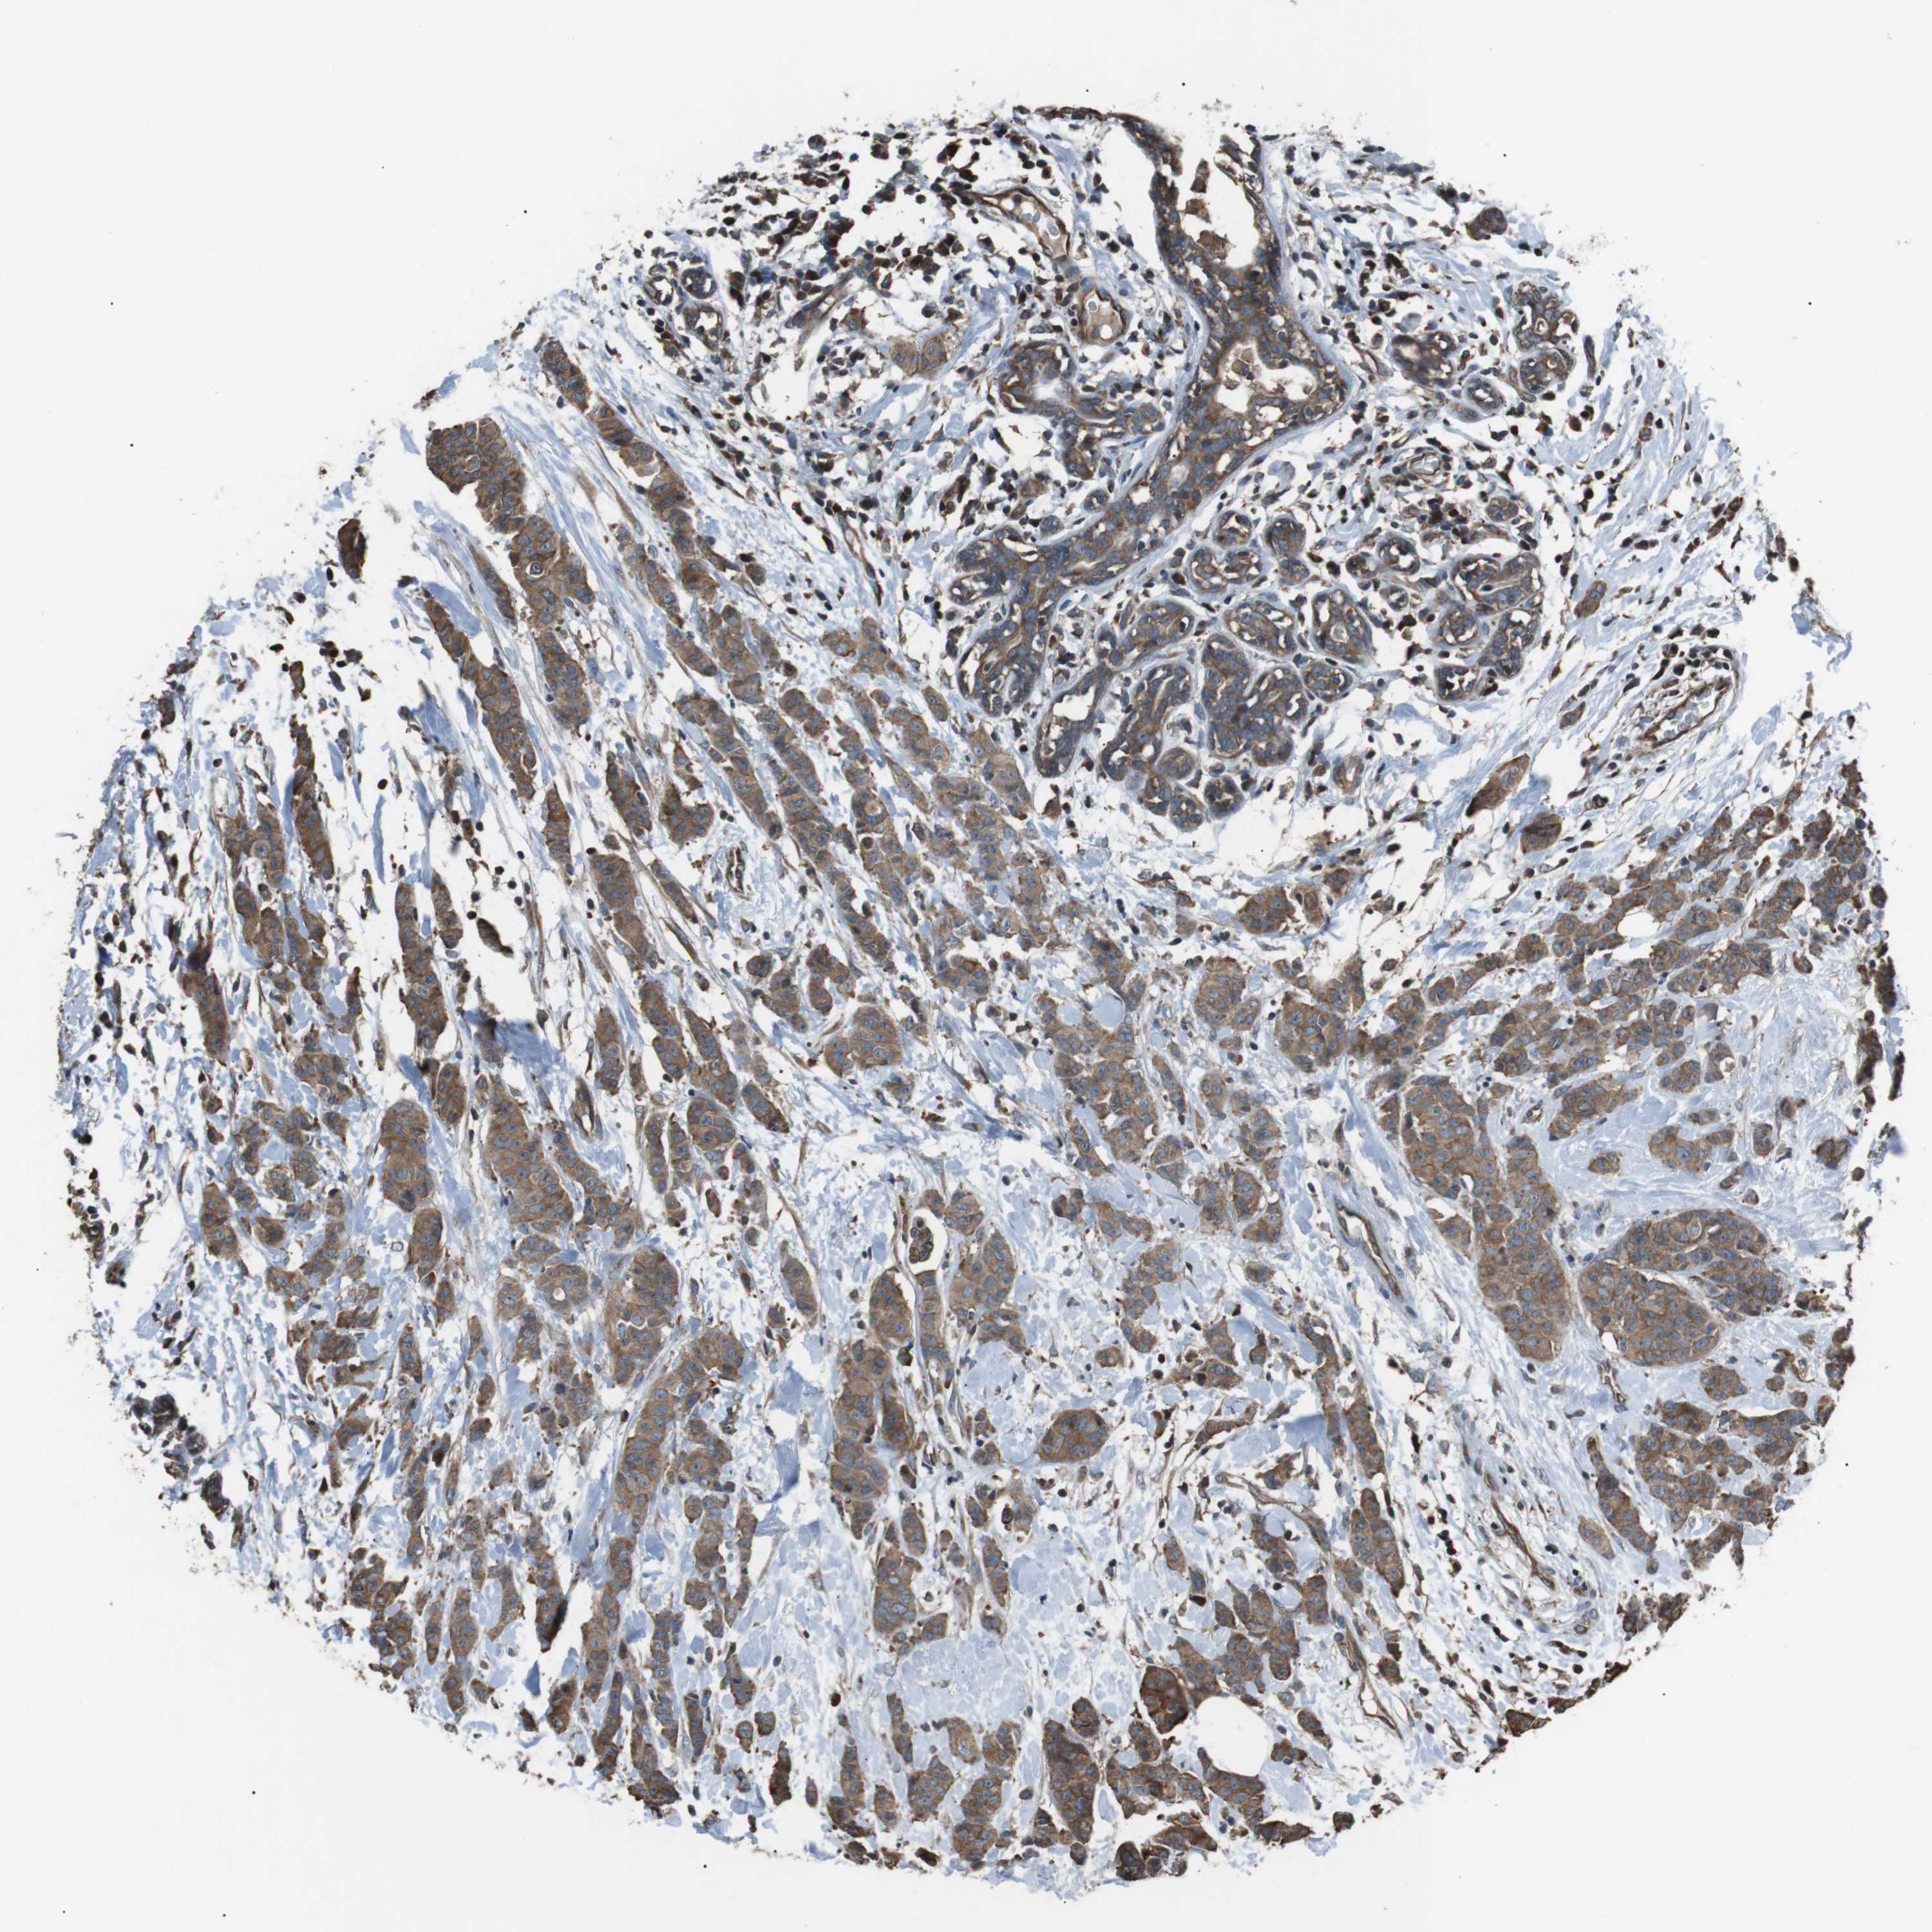

BRCA TCGA BRCA VALIDATION PROTEIN EXPRESSION

ANTIBODIES

AND

VALIDATION